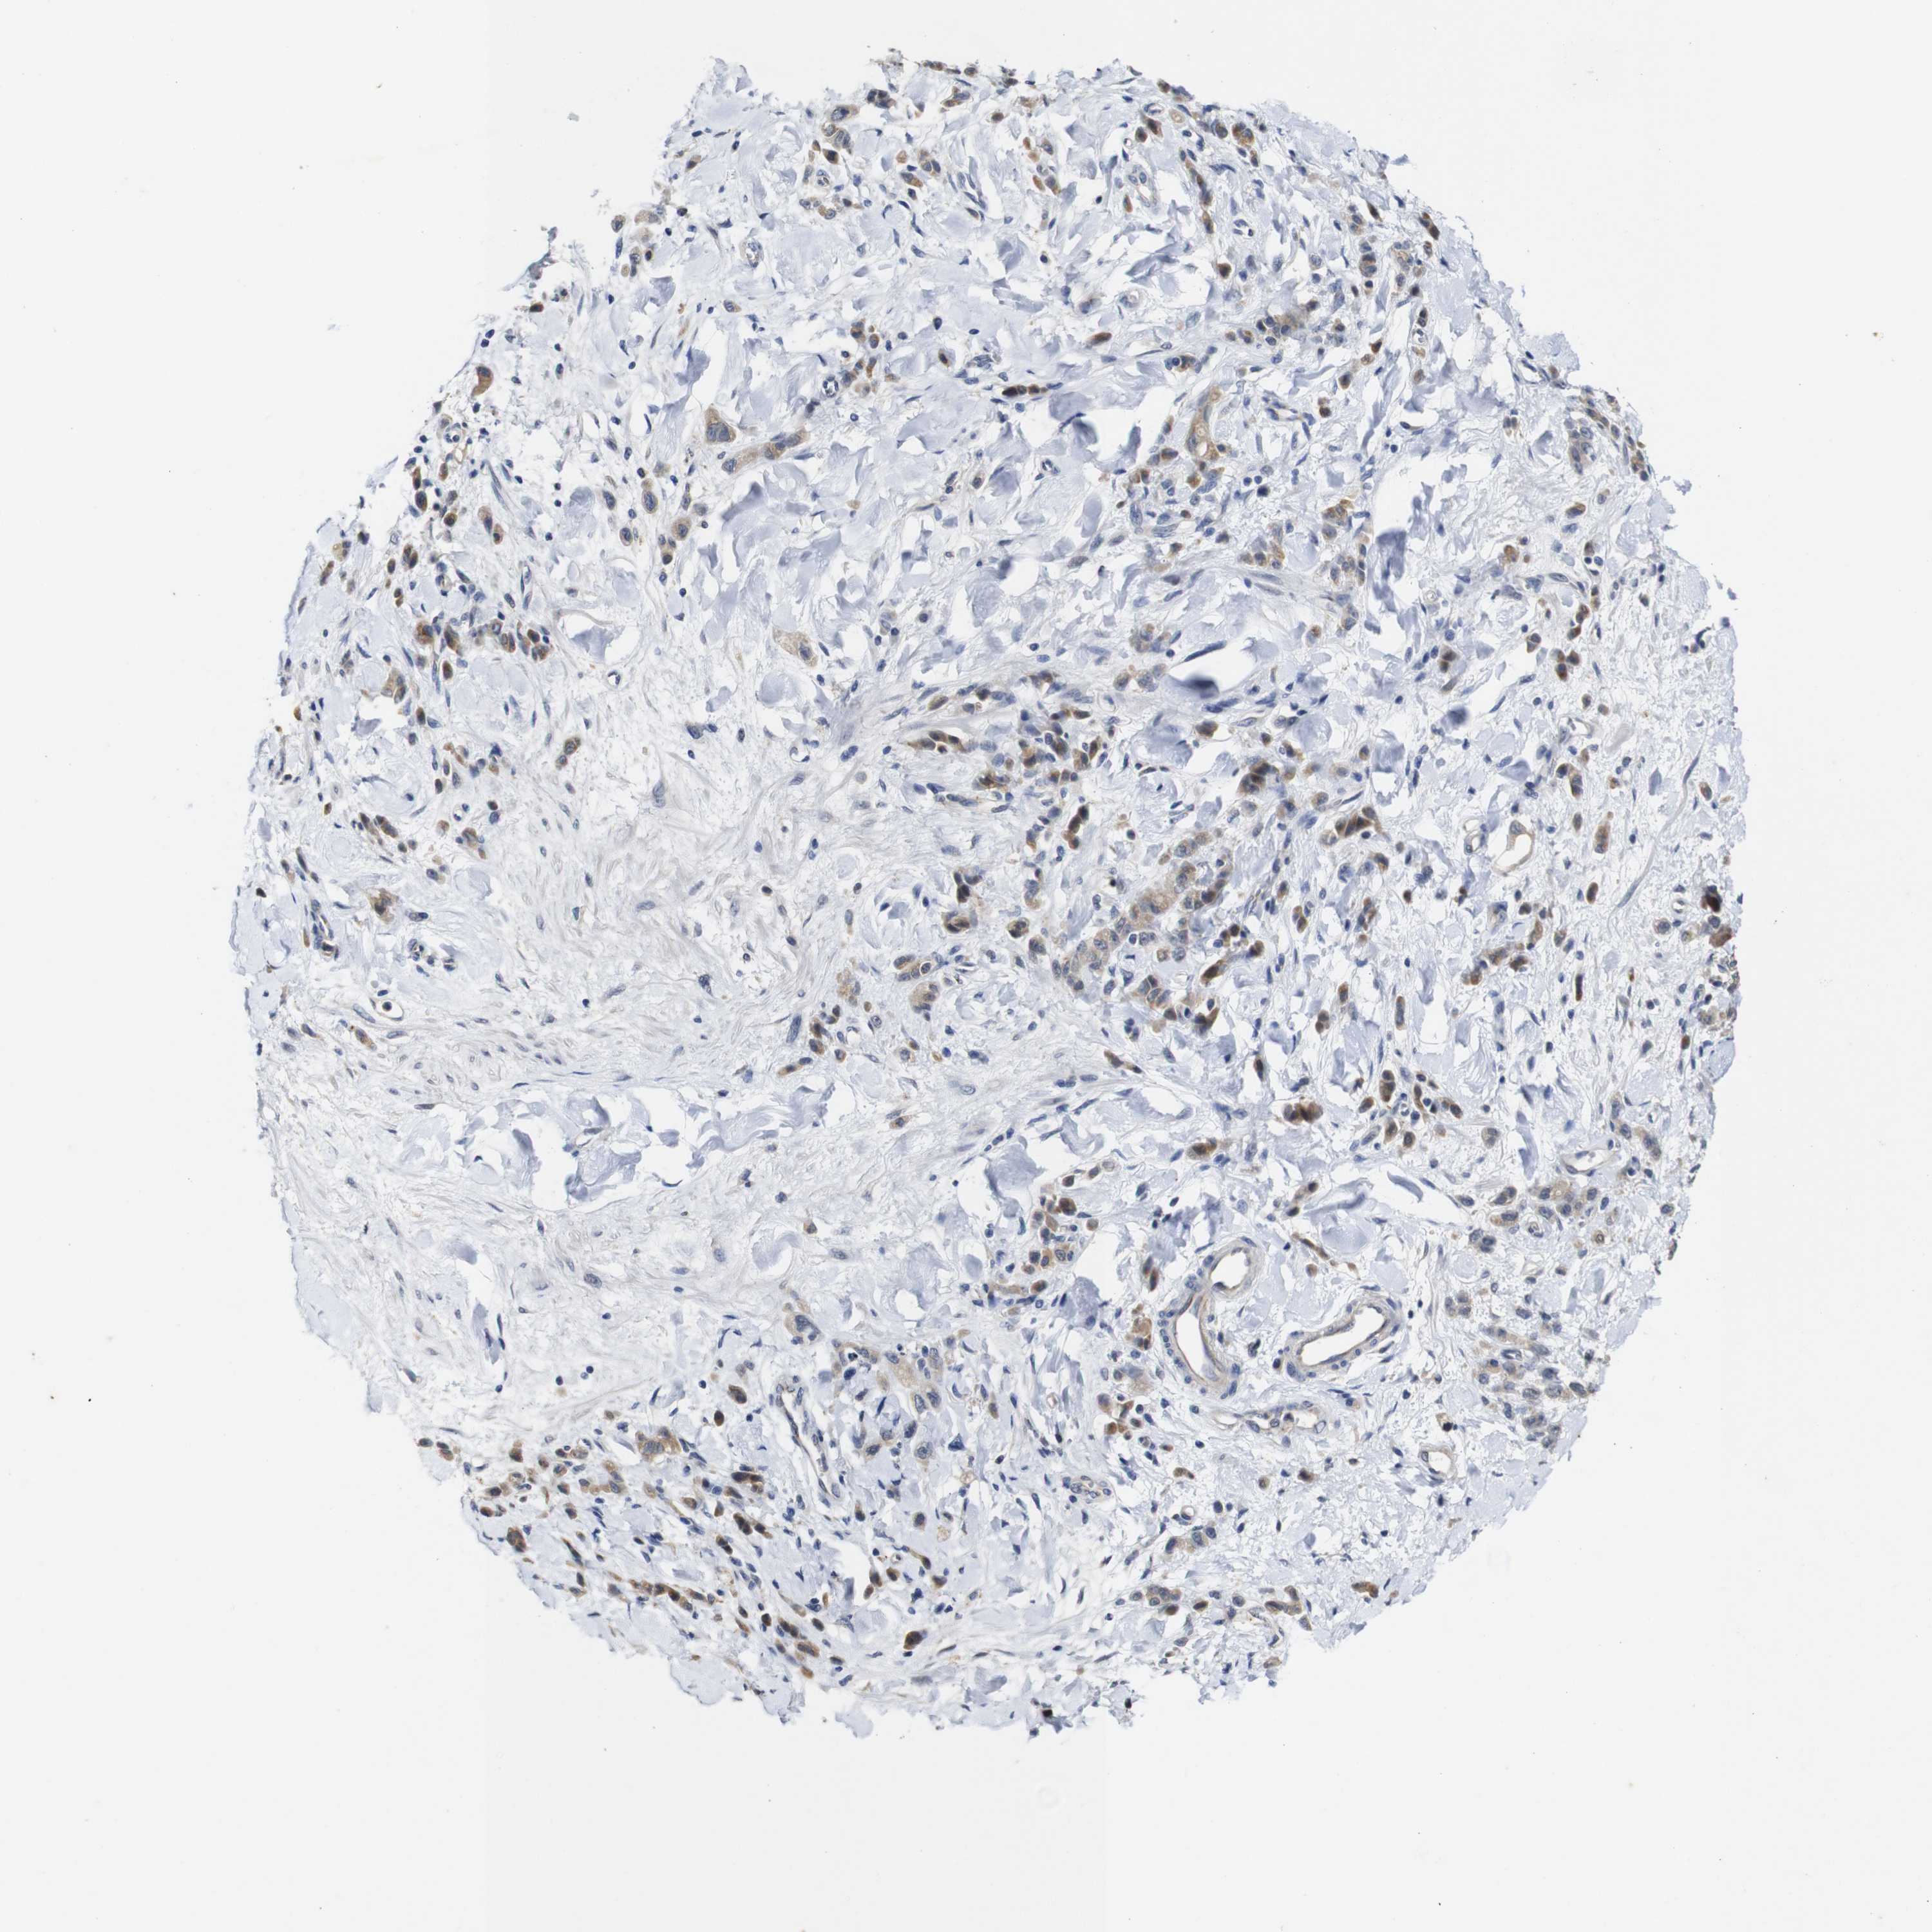

STOMACH CANCER - Protein expressioni

A mouse-over function shows sample information and annotation data. Click on an image to view it in a full screen mode. Samples can be filtered based on level of antibody staining by selecting one or several of the following categories: high, medium, low and not detected. The assay and annotation is described here.

Note that samples used for immunohistochemistry by the Human Protein Atlas do not correspond to samples in the TCGA dataset.

Antibody stainingi

Antibody staining in the annotated cell types in the current human tissue is reported as not detected, low, medium, or high, based on conventional immunohistochemistry profiling in selected tissues. This score is based on the combination of the staining intensity and fraction of stained cells.

Each image is clickable and will lead to virtual microscopy that enables deeper exploration of all samples and also displays staining intensity scores, fraction scores and subcellular localization as well as patient and tissue information for each sample.

Antibody HPA067869

Antibody CAB009499

Staining

High

Medium

Low

Not detected

Intensity

Strong

Moderate

Weak

Negative

Quantity

>75%

75%-25%

<25%

None

Location

Nuclear

Cytoplasmic/membranous

Cytoplasmic/membranous,nuclear

Adenocarcinoma, NOS

Adenocarcinoma, High grade